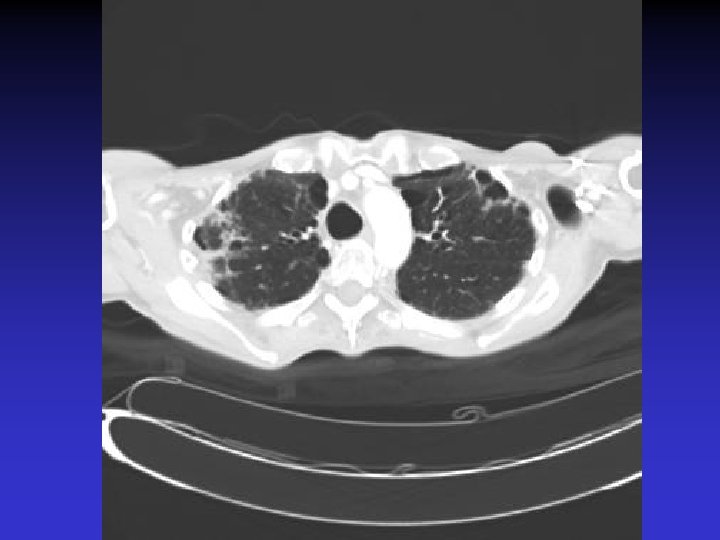

NTM lung disease n n MAC, M. kansasii, M. abscessus >50 years, ? M vs. F Symptoms n variable, nonspecific n chronic or reoccurring cough n sputum production, fatigue, malaise, dyspnea, fever, hemoptysis, chest pain, wt loss n more constitutional symptoms with advancing disease n evaluation complicated by sx of coexisting lung disease CXR n Fibrocavitary – often like MTB, but may be dense airspace dz or solitary cavity w/o cavitation n Nodular/bronchietatic – typical MAC, usu. mid-lower lung fields, +/- cavitation